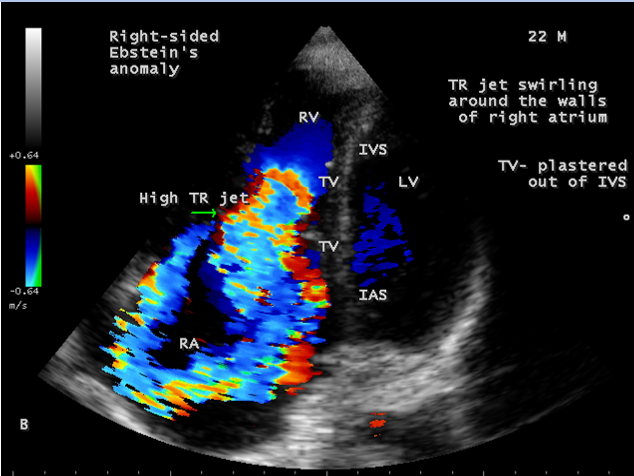

A 22-year old acyanotic male was presented with features of right heart failure and a grade 3/6 systolic murmur at lower left sternal border. 2D echocardiography revealed a normally attached septal tricuspid leaflet (STL), but tethered to the ventricular wall suggesting an Ebstein’s anomaly with severe tricuspid regurgitation swirling around the lateral wall of right atrium and interatrial septum, and a dilated atrium and atrialized RV (right ventricle) as shown in Figures 4 to 8.

The tricuspid orifice is typically incompetent as in Figures 3, 5 and 10, occasionally stenotic, and rarely imperforate as in Figure 16 [44],[45]. The true anatomic tricuspid annulus occupies its normal position at the right atrioventricular junction and it is less well defined than in a normal heart. The annulus tends to be appreciably dilated and contribute to the development of valvular incompetence. In extreme downward displacement of posterior and septal leaflets, the closure of the tricuspid annulus depends on the size and potential excursion of anterior leaflet. When the chordal attachments are short and the leaflets contain multiple or large fenestrations, adequate valve closure is impossible to achieve and varying degrees of regurgitation results. Color flow imaging and Doppler interrogation can establish the relatively low velocity regurgitant flow as in Figure 6, which begins at the level of the displaced septal and posterior leaflets as in Figures 5 and 10 and courses through the atrialized right ventricle into the right atrium proper as shown in Figure 5. Tricuspid regurgitation increases by annular dilatation [46]. During contraction of the atrium, the atrialized portion of the right ventricle balloons out and acts as a passive reservoir. Functional improvement of right ventricle depends on the severity of tricuspid regurgitation and on the ratio of the combined areas of right atrium and atrialized right ventricle relative to the areas of functional right ventricle and left ventricle [47]. Celermajer, et al described an echocardiographic grading score for neonates with Ebstein’s anomaly as shown in the Table 5 [48].

The functional impairement of right ventricle and regurgitation of tricuspid valve retard the forward flow and the overall effect is right atrial dilatation as shown in Figure 4. In many cases, the right atrial enlargement is extensive, but the mural thrombus is not a feature even in right ventricular dilatation. The enlarging right atrium becomes sufficiently compliant to accomodate a large volume of regurgitant flow with little or no increase in pressure as shown in Figure 6., In patients with marked Ebstein’s malformation and severe tricuspid regurgitation, liver and portal circulation are extensively affected, congestive hepatosplenomegaly and microscopic hepatic fibrosis eventually occurs in chronic cases with hypersplenism [49].